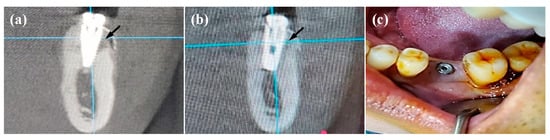

The CBCT image taken from the IDCT-modified Ti implant after immediate placement is shown in Figure 6a. The CBCT image revealed a radiolucency in the buccal dental implant site (as indicated by the black arrow), indicating that the site is unsupported by intact bone. After four months of post-placement, the CBCT image showed a more radiopaque image of the buccal dental implant site (Figure 6b, black arrow), which previously appeared more radiolucent, indicating new bone formation in this area. Moreover, the clinical condition after four months also indicated that good tissue healing around the IDCT-modified Ti implant was evident, as illustrated in Figure 6c.

Figure 6.

The cone-beam computerized tomography images taken from the left mandibular premolar with the IDCT-modified Ti implant after (a) immediate placement, (b) four months placement, and (c) clinical evaluation (four months placement).